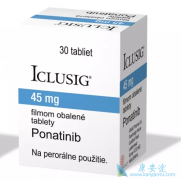

普钠替尼是一种新型的激酶抑制剂,它的药品结构与 伊马替尼 非常相似。有医疗研究人员调查显示, 普钠替尼 可用于抑制SRC和ABL等多种激酶。基于细胞的突变筛查研究发现,当ponatinib达到药理学有效浓度水平时,可抑制所有BCR-ABL突变的亚克隆生长。到完 ...